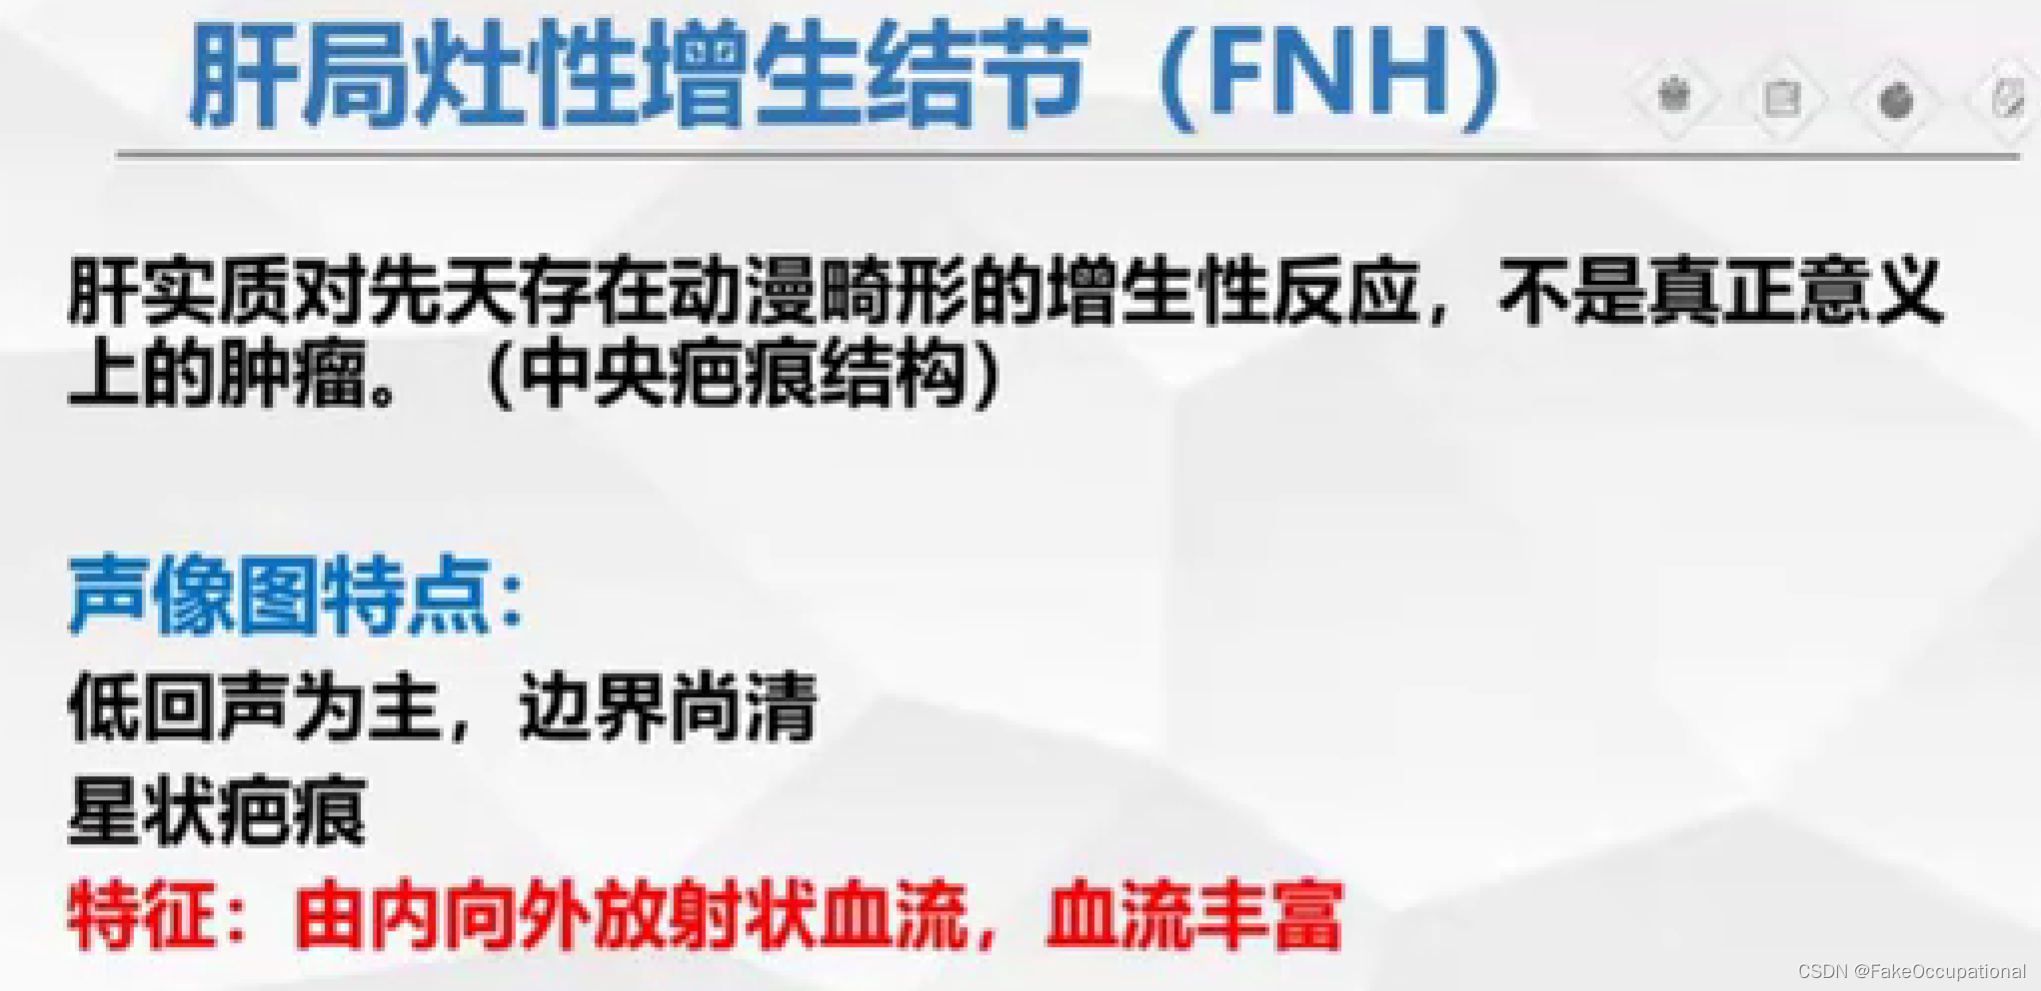

- 超声更多起一个筛查的作用,定性需要造影或者其他设备的辅助